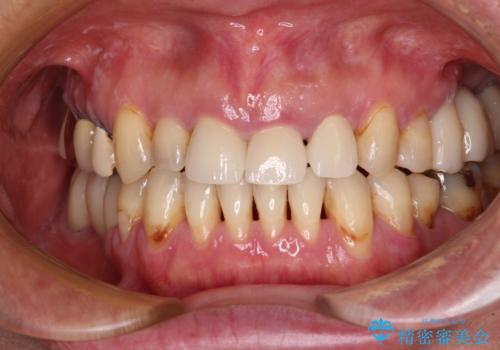

- 前歯のクラウン周りに歯肉が腫れていることを気にして来院された患者様です。

元々磨き残しによる歯肉の腫脹がありましたが、クラウンが歯肉深くに装着されていたため、特に腫脹が目立っていました。

仮歯に置き換えた際に歯周外科処置を行い、歯肉の腫脹が落ち着いたことを確認してオールセラミッククラウンにて補綴することとしました。